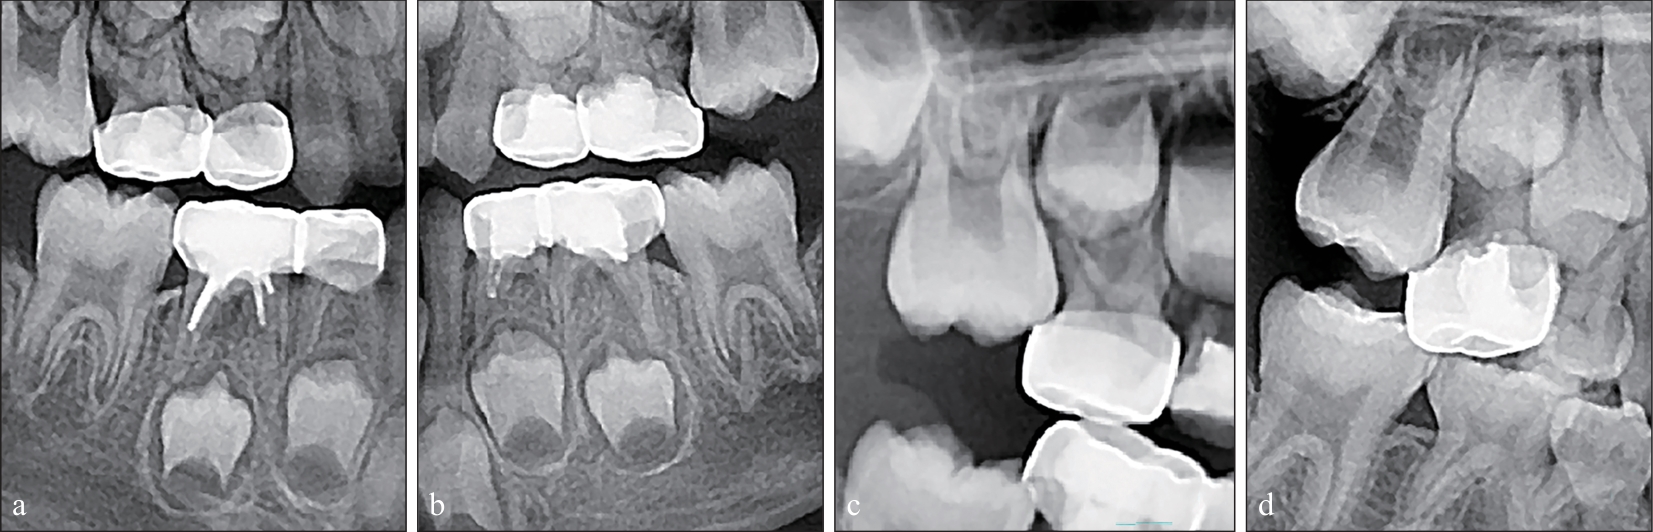

目的 分析第二乳磨牙行金属预成冠修复后,相邻第一恒磨牙发生异位萌出的相关因素。 方法 试验组纳入19例患者共25颗第二乳磨牙,均为行金属预成冠修复且相邻第一恒磨牙发生异位萌出者;对照组纳入19例患者共29颗第二乳磨牙,均为行金属预成冠修复且相邻第一恒磨牙正常萌出者。对所有研究对象的曲面体层片进行分析,评价患者年龄、性别、多象限发生第一恒磨牙异位萌出情况、预成冠远中台阶情况,测量第一恒磨牙倾斜角度、第二乳磨牙倾斜角度及两牙间牙体长轴交角。使用Pearson卡方检验及成组t检验对数据进行统计学分析。 结果 预成冠远中台阶与相邻第一恒磨牙发生异位萌出呈正相关关系,OR=9.14(95%置信区间为1.06~79.26,P< 0.05)。与对照组比较,试验组上颌第一恒磨牙与第二乳磨牙牙体长轴夹角(均值为6.51°±4.46°)偏小(P<0.05),下颌第一恒磨牙倾斜角度(均值为43.66°±10.56°)更偏近中(P<0.05),下颌第一恒磨牙与第二乳磨牙牙体长轴夹角(均值为25.39°±10.79°)显著增大(P<0.05)。 结论 在第二乳磨牙行金属预成冠修复前,需评估对应第一恒磨牙发生异位萌出的风险,尤其当患者已有其余象限发生第一恒磨牙异位萌出者。当上颌第一恒磨牙和第二乳磨牙的牙体长轴夹角过小,下颌第一恒磨牙倾斜角度过大,或下颌第一恒磨牙与第二乳磨牙的牙体长轴夹角过大时,应尽量减少使用金属预成冠修复,或采取相应预防措施,尤其要注意预成冠修复时远中边缘的适应性,避免远中面台阶形成。

Objective This study aims to analyze the related factors of ectopic eruption of adjacent first permanent molars after the restoration of stainless-steel crowns of the second primary molars. Methods The experimental group consisted of 19 patients, and 25 second primary molars with stainless steel crown restorations were examined. The patients presented with ectopic eruption of the corresponding first permanent molars. The control group included 19 patients, from whom 29 second primary molars with stainless steel crown restorations were examined. Notably, the corresponding first permanent molars erupted normally. The panoramic radiographs of all participants were analyzed, and va-riables, such as patient age, gender, ectopic eruption positions of the first permanent molars, and the distal margi-nal adaptation of the stainless-steel crowns, were asses-sed. The tilt angles of the first permanent molars, second primary molars, and the intersection angle between the long axes of the two teeth were measured. Data were subjected to statistical analysis using Pearson’s chi-square test and independent t-tests. Results A significant positive correlation was identified between the distal marginal adaptation of the stainless-steel crowns and the ectopic eruption of the corresponding first permanent molar (OR=9.14, 95% CI: 1.06-79.26, P<0.05). Compared with the control group, the experimental group exhibited a smaller angle between the long axes of the maxillary first permanent molar and the second primary molar (6.51°±4.46°, P<0.05). Additionally, the mandibular first permanent molar had a more pronounced inclination (43.66°±10.56°, P<0.05), and the angle between the long axes of the mandibular first permanent molar and the second primary molar was significantly larger (25.39°±10.79°, P<0.05) in the experimental group. Conclusion Prior to the restoration of second primary molars with stainless steel crowns, evaluating the potential risk of ectopic eruption of the corresponding first permanent molar is essential. This step is particularly important when ectopic eruption is present in the remaining quadrants. When the angle between the long axes of the maxillary first permanent molar and the second primary molar is excessively small, the inclination of the mandibular first permanent molar is extremely large, or the angle between the long axes of the mandibular first permanent molar and the second primary molar is extremely large, the use of stainless-steel crowns should be minimized, or preventive measures should be considered. Special attention must be given to the distal marginal adaptation during stainless steel crown restoration to prevent the formation of steps on the distal surfaces.